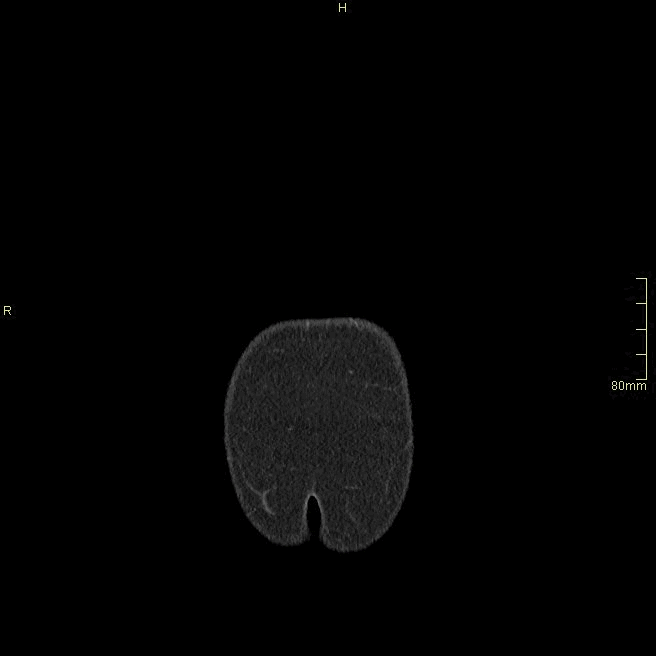

Chest/Abdomen Angiogram (Coronal)